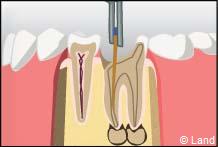

La pulpe est atteinte par la progression de la carie. Il y a donc un risque non négligeable de voir apparaître un foyer infectieux au bout de la racine.

1° Le chirurgien-dentiste va donc procéder à la dévitalisation* de la dent ; en clair il va extirper de la partie centrale de la dent avec les instruments adéquats, soit manuellement soit mécaniquement, la pulpe dentaire constituée de filets nerveux et de très fins vaisseaux sanguins. Cette étape permet d’enlever la totalité des tissus nécrosés ou infectés et de procéder à un nettoyage soigneux anti bactérien.